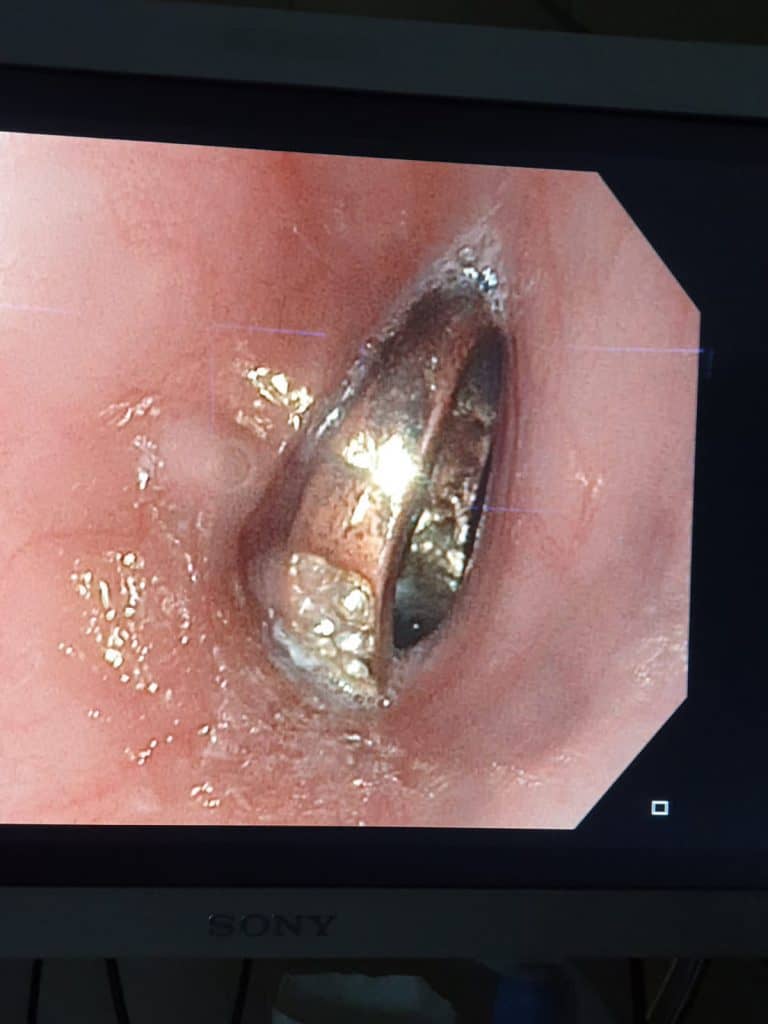

לאחר שחשה כאבים באיזור החזה היא הובהלה לבית החולים, שם בוצעו לה צילומים שהראו כי הטבעת נתקעה בושט. בעקבות האבחנה הוחלט לבצע פעולת גסטרוסקופיה בהרדמה מלאה להוצאת הטבעת.

בשל היותה של הטבעת חתוכה, נדרשה תשומת לב גדולה יותר ורמת דיוק גבוהה, על מנת שלא לפצוע את הנתיב בו הוצאה הטבעת החוצה.

מי שביצע בהצלחה את הפעולה בהרדמה כללית ובחדר הניתוח, היה רופא גסטרו ילדים במרכז הרפואי זיו, ד"ר ביאן הינו, בעזרת אחראית מכון גסטרו האחות שרי טרבלסי וצוות חדר הניתוח. שירה בת ה-6 אושפזה להשגחה באותו הלילה ושחררה למחרת בריאה ושלמה.

ד"ר ביאן הינו אמר לאחר האירוע, "ילדים בולעים גופים זרים שונים, אבל יש כמה שדורשים התייחסות מיוחדת והוצאה אנדוסקופית מיידית כשהם בטווח השגה. במקרה הזה, הילדה בת ה-6 בלעה טבעת שנתקעה בושט ולכן נדרשה הוצאה אנדוסקופית בהרדמה כללית בחדר. על ההורים והמטפלים מוטלת החובה לשמור היטב על ילדיהם מסכנות אלו".